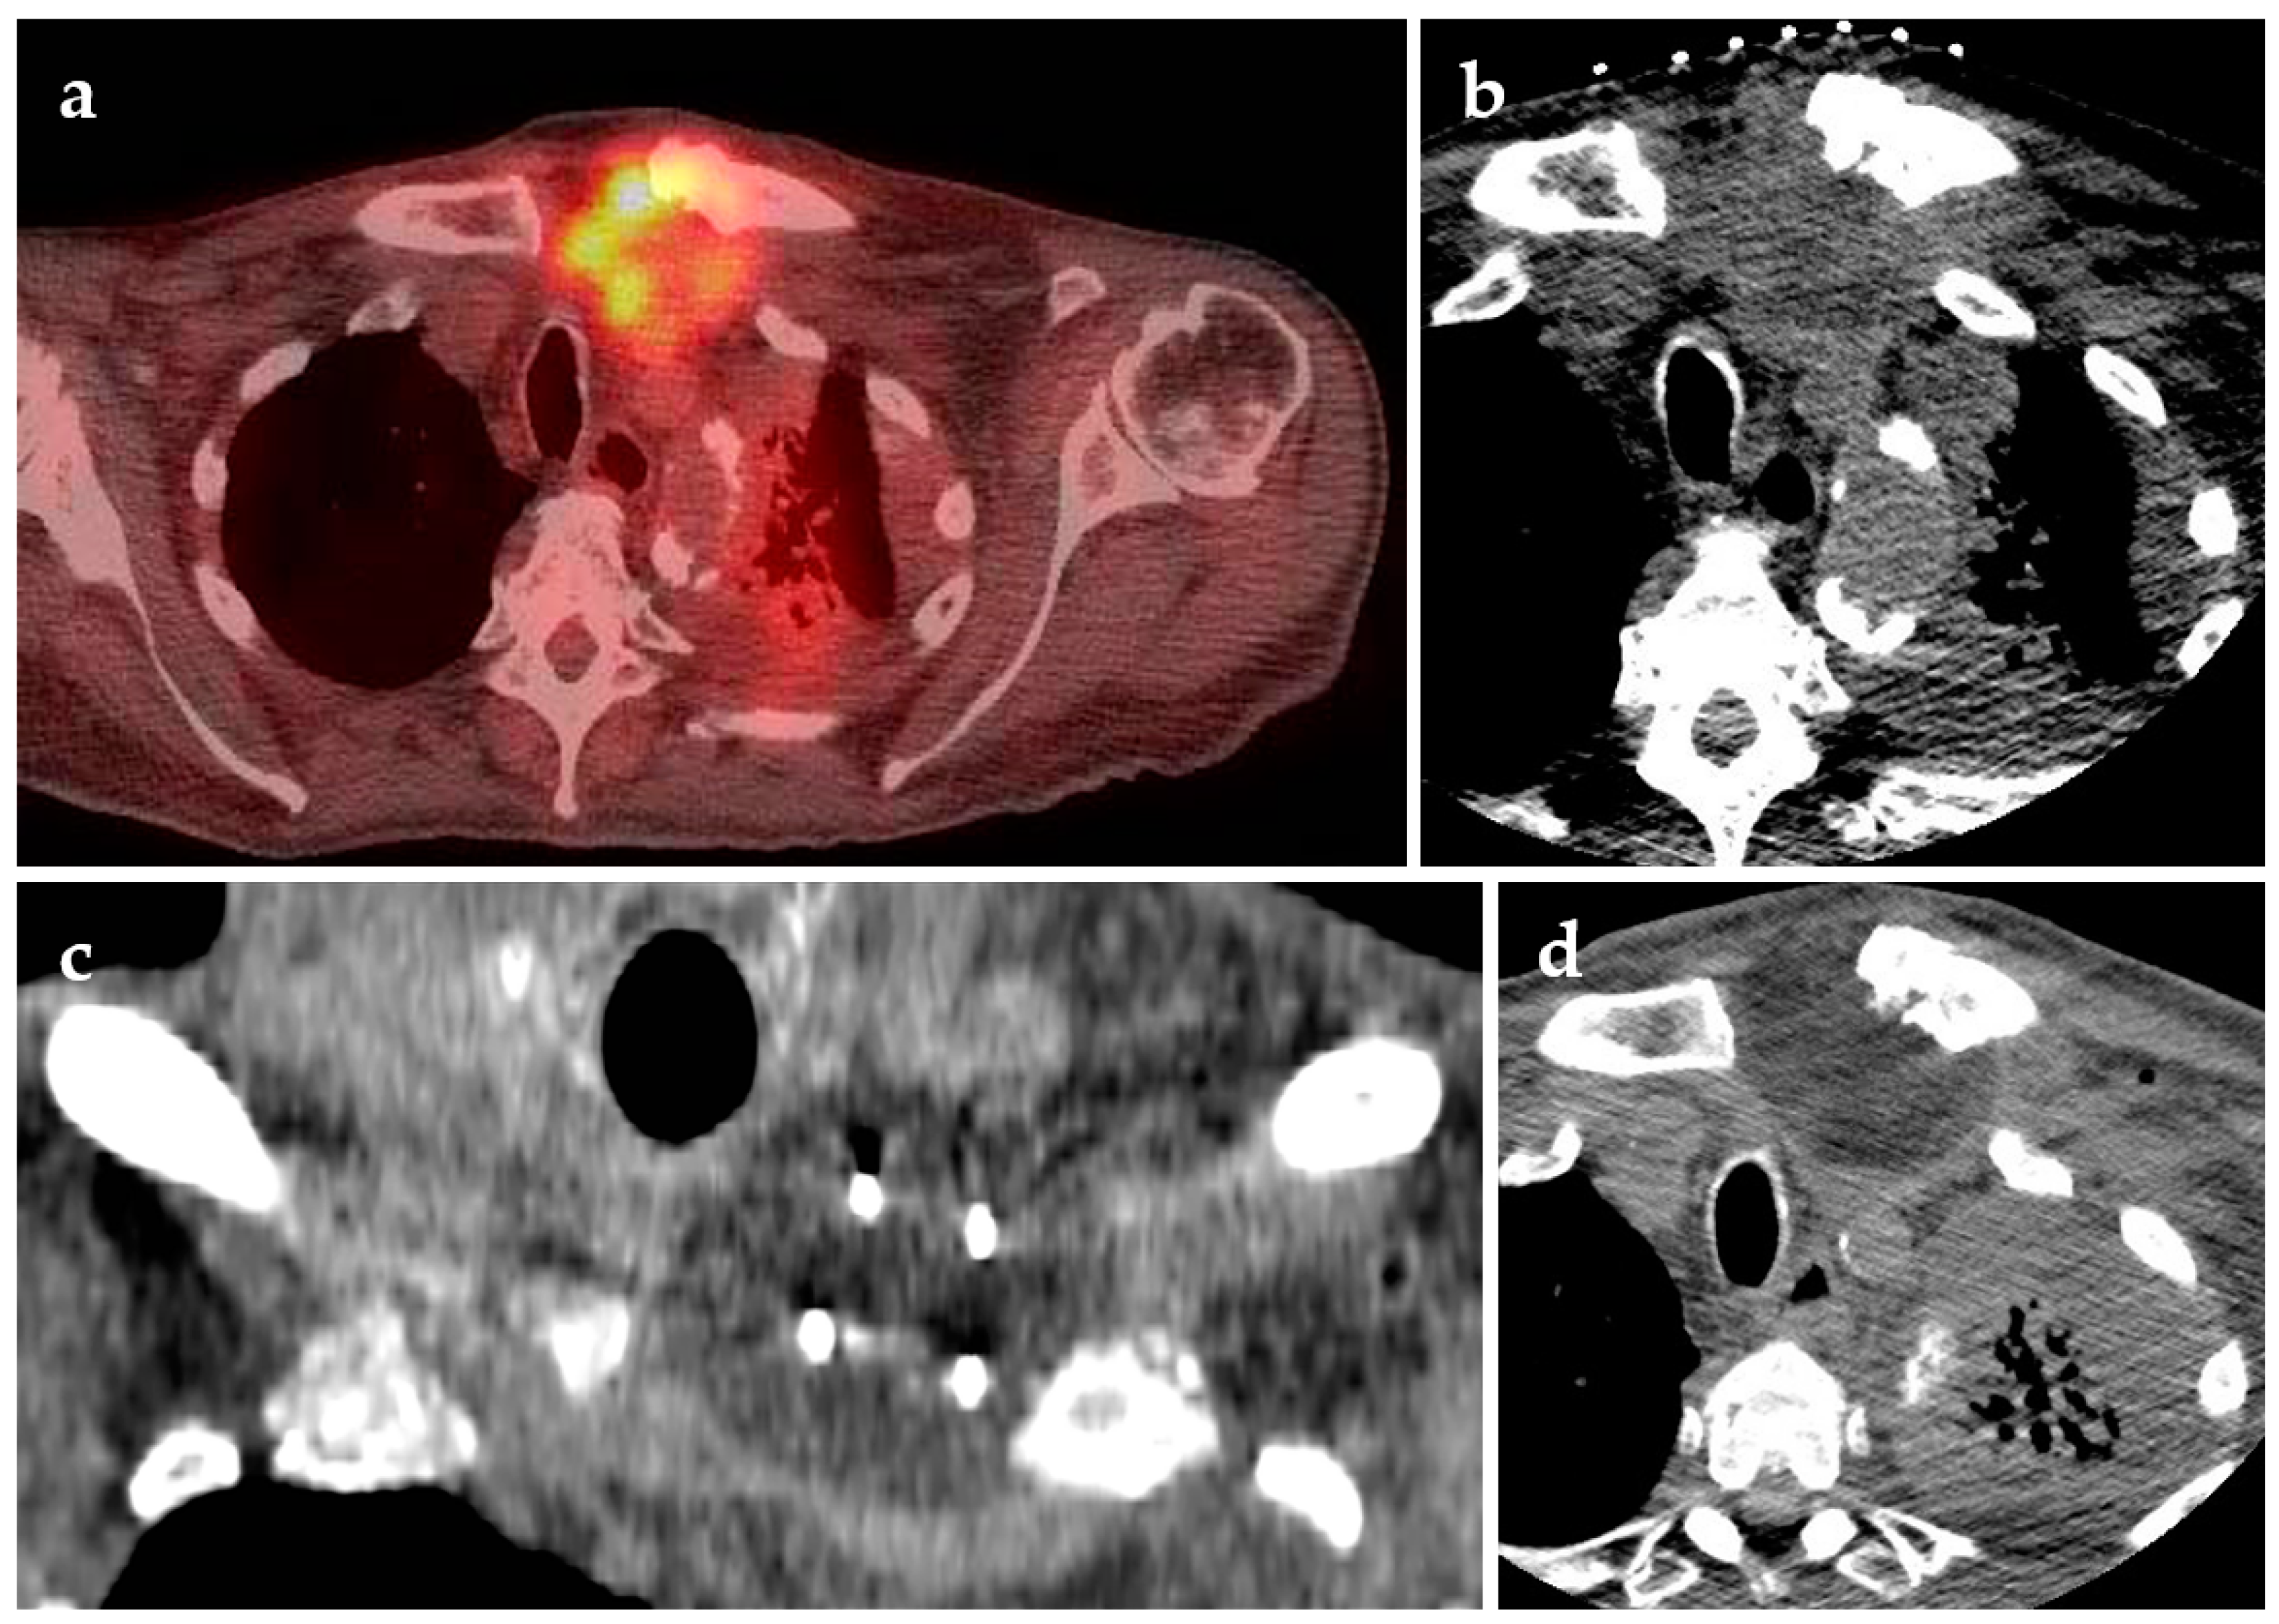

4.1. Cryoablation